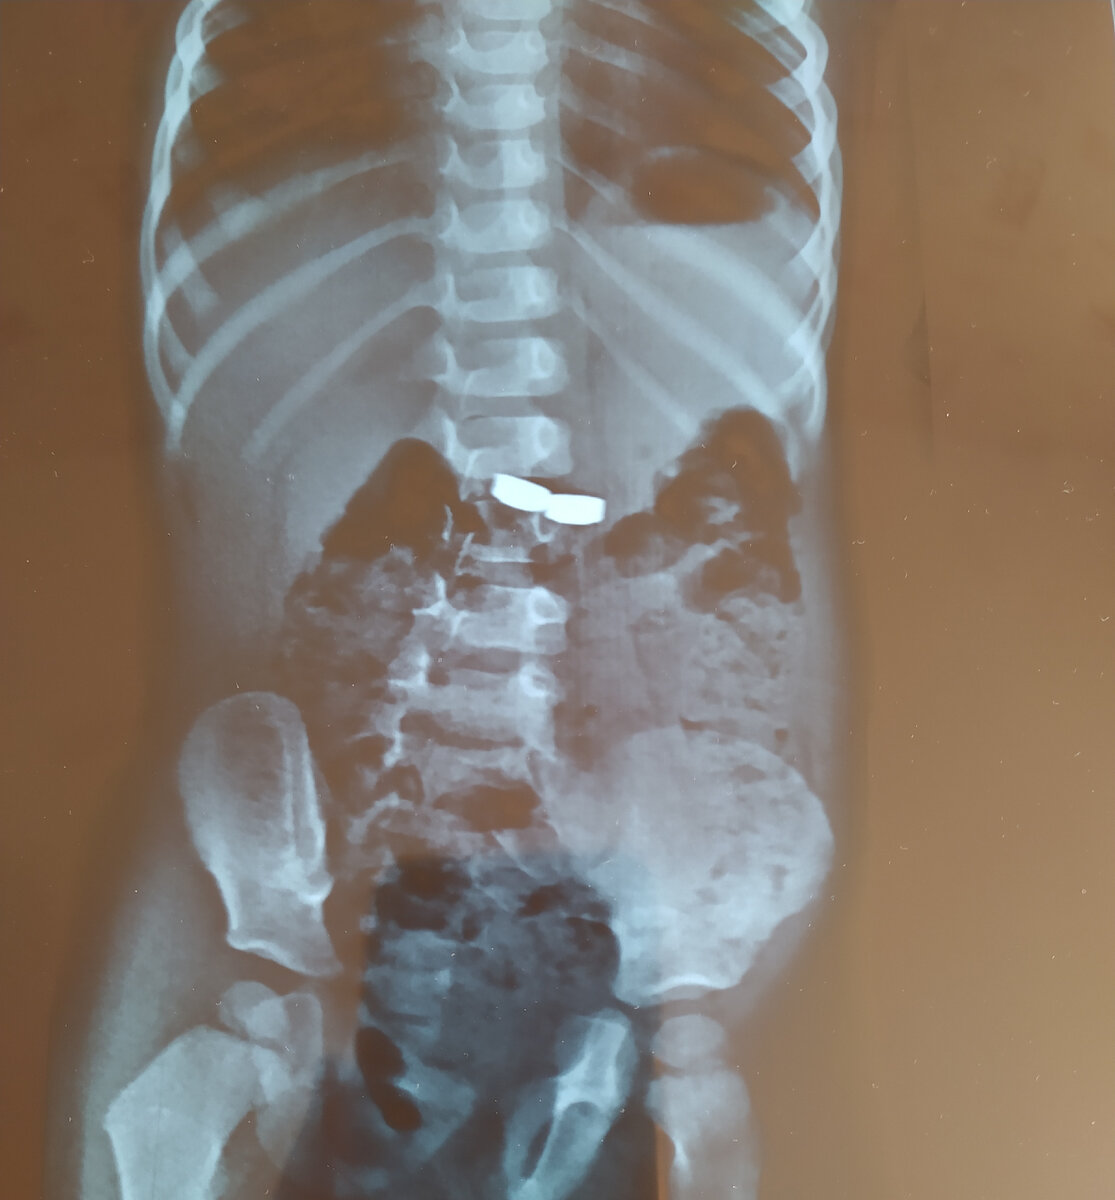

В общем, не буду тянуть кота за хвост свой рассказ. Две последние маленькие круглые батарейки ребёнок просто съел, пока я прятала другие.

Батарейки хорошо видны на рентгеновском снимке

От руководства отказались, и просто выслали бригаду. Бригада отвезла в детскую областную больницу. Там сделали рентген, увидели на снимке батарейки, пригласили хирурга и предложили отвезти в другую больницу ... ждать под присмотром, когда они выйдут естественным путём. Финиш.